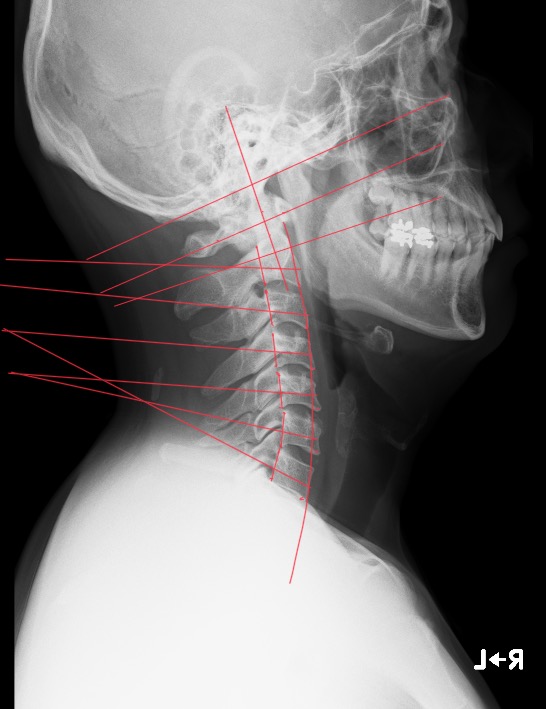

上記頚椎側面像、後頭骨から頚椎2番までの分析、頚椎2番から胸椎2番までの形状と位置を確認し、サブラクセーションの可能性を導き出します。